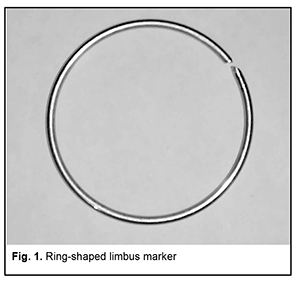

http://doi.org/10.31288/oftalmolzh202036164 Received: 26 February 2020; Published on-line: 24 June 2020 A method of marking the limbus during X-ray localization of IOFB in the presence of apparent chemosis or scleral subconjunctival hemorrhage N.V. Malachkova, I.A. Gabruk; I.I. Gabruk; O.O. Andrushkova, Pirogov Vinnytsia Regional Clinical Hospital; Vinnytsia (Ukraine) Pirogov National Medical University; Vinnytsia (Ukraine) E-mail: illyagabruk@i.ua TO CITE THIS ARTICLE: Malachkova N.V., Gabruk I.A., Gabruk I.I., Andrushkova O.O. A method of marking the limbus during X-ray localization of IOFB in the presence of apparent chemosis or scleral subconjunctival hemorrhage. J.ophthalmol.(Ukraine).2020;3:61-64. http://doi.org/10.31288/oftalmolzh202036164 The method proposed for marking the limbus during X-ray localization of IOFB in the presence of apparent chemosis or scleral subconjunctival hemorrhage is based on the use of a ring-shaped limbus marker made from 0.5-0.7-mm stainless steel wire. Rings with external diameters of 10, 11 and 12 mm are used for examining eyes of different sizes. A ring of the appropriate size is placed on the cornea against the limbus to perform X-ray examination. It is well fit in the specified position due to hypertrophy of the conjunctiva surrounding the cornea, and corresponds to the conjunctival attachment to the limbus. Orbit X-ray is performed, quality of X-ray films is assessed and IOFB position in the eye is calculated using the technique of Comberg-Baltin or Abalikhin-Pivovarov. In 12 patients, IOFB was successfully removed based on the data obtained from the use of this method. The accuracy of IOFB X-ray localization by means of the ring-shaped limbus marker was found to be the same as that by means of the Baltin’s prosthesis. Keywords: X-ray localization of intraocular foreign bodies, ring-shaped limbus marker

Introduction Ocular trauma is still a leading cause of loss of vision and legal blindness and vision impairment. Intraocular foreign bodies (IOFBs; such as metal, glass, rock, etc.) are seen in 15%-40% of penetrating ocular injuries [1, 2]. IOFBs sized 1-2 mm are most common and can cause early and late complications (endophthalmitis, metallosis, etc.) which are more significant in terms of their effect on health than the trauma caused by such a body itself. IOFBs sized more than 5 mm commonly cause significant damage to the eye, and may lead to loss of not only vision, but also of the whole eye. Accurate IOFB localization is essential for the success of IOFB removal. Until recently, orbit X-ray in two views using the Comberg-Baltin prosthesis was the primary imaging modality for localizing radiopaque IOFBs. Although other modalities can be used today for localizing radiopaque IOFBs, they do have certain diagnostic disadvantages. Because the X-ray method of foreign body localization is widely available, cost-effective, and offers sufficient accuracy for surgical planning, it is still relevant. It is used in combination with contemporary imaging modalities (CT, ultrasound, etc.) and, if these are unavailable, it can be used as the primary imaging modality. Although the ultrasound method is, undoubtedly, of value in localizing IOFBs, especially radiopaque ones, it cannot localize the IOFB accurately enough to remove the latter immediately. In addition, it is effective only if combined with the X-ray method. Computed tomography (CT) scan provides more differentiated images of ocular tissue and media, and can identify IOFB and precisely locate it with respect to the adjacent ocular structures in most cases. CT is the indispensable imaging examination technique in the presence of numerous IOFBs, but is not always effective in determining IOFB size and shape. In CT scans, a foreign body sized less than 3 mm appears as a regular round body, and that sized 3 to 7 mm appears as an irregularly round or oval-shaped body, although the actual size and shape may differ from those seen in the CT. CT images of metal IOFBs often suffer from bright and dark streak artifacts that radiate from the shadow of metal IOFB. If there is any possibility that the foreign body may be metallic, magnetic resonance imaging (MRI) should not be performed because of possible movement of the object and consequent damage to intraocular structures. Scleral subconjunctival hemorrhage is more commonly caused by larger IOFBs. In addition, hypertrophy of the scleral conjunctiva surrounding the limbus may arise from other causes such as allergic response, burns, consequences of severe concussion, etc. Marking the position at the limbus presents some difficulties in the presence of apparent chemosis or scleral subconjunctival hemorrhage. As it is difficult or impossible to make the Baltin prosthesis adjacent to the limbus under these circumstances, other methods have been proposed for marking the position at the limbus. Baltin [3] proposed to apply bismuth pulp to mark the limbus at 6 and 12 o’clock axes with a (preferably plastic) probe when the lids are separated with eye speculum. Bismuth pulp spreads over the eye and is washed away by tears rather frequently. In addition, the eye must be kept immobile during examination, which is almost impossible. Vodovozov [4] proposed to mix bismuth or barium sulfate with nitro-glue or collodion, make small silver-paper half-discs and soak them in this mixture, and use them to mark the limbus. These adhere well to the limbus, are not washed away by tears, and exhibit no displacement during movements of the eye. Poliak [5-6] proposed to introduce T-shaped studs beneath the conjunctiva at the limbus at 3 and 9 o’clock axes. Adhering, suturing or fastening various radiopaque markers at the limbus causes incongruous shadows on X-ray films, and can result in increased damage to the eye. Because radiopaque objects are placed by sight and hands and in one plane, approximately at certain meridians, location of the IOFB in the eye is estimated with a significant error. Marking the center of the cornea with a probe, dressing forceps, or other methods (Plittas, 1941; Bogatin, 1949; Madroszkiewiz, 1954, etc) have not been widely implemented due to their small effect [7]. A limbal ring (internal diameter, 12 mm) made of 1-mm thick wire, which is sutured or adhered to the conjunctival sclera, cannot mark the limbus in cases of hypertrophy of the scleral conjunctiva, and it is difficult or impossible to make the ring adjacent to the limbus. In addition, it should not be used in the presence of fresh, gaping wound [8-10]. Gardona and Trokel [11] used a soft vacuum lens for X-ray localization of foreign bodies in eyes with maintained corneal sphericity. Such a lens remains well secured and does not change its position over the cornea, which facilitates adequate localization of the IOFB. Taking into account the relevance of the problem, we have been looking for a new way to solve it. We made a corneal prosthesis (limbus marker; Innovation Proposal No. 556/54 dated 12.07.1989), which is a rigid corneal contact lens (optical power, 0D; diameter, 11 mm; thickness, 0.3-0.35) made of polymethylmethacrylate. The lens has 0.5-mm lead marks in four quadrants (3, 6, 9 and 12 o’clock); lead mark edges and lens edges coincide with each other. The distance between external contours of adjacent marks is 11 mm, and the distance between internal contours is 10 mm. The prosthesis is well fit in the specified position over the cornea during X-ray examination. It can be used if the conjunctiva and lens are abnormally spherical in shape (chemosis and/or subconjunctival hemorrhage) and in the presence of a fresh scleral wound. The purpose of the study was to improve the accuracy of X-ray localization of foreign bodies in the presence of apparent chemosis or scleral subconjunctival hemorrhage through the use of the ring-shaped limbus marker. Material and Methods We proposed a method for marking the limbus during X-ray localization of foreign bodies in the presence of apparent chemosis or scleral subconjunctival hemorrhage through the use of the ring-shaped limbus marker (Patent of Ukraine No. 12,015 issued 25.10.2017; Bulletin No. 20). The ring is made from 0.5-0.7-mm stainless steel wire. Rings with external diameters of 10, 11 and 12 mm were made for examining eyes of different sizes. The examination procedure was as follows. After epibulbar anesthesia, a sterile ring-shaped limbus marker of the appropriate size was placed on the cornea against the limbus. It was well fit in the specified position due to hypertrophy of the conjunctiva surrounding the cornea, and corresponded to the conjunctival attachment to the limbus. The posterior-to-anterior (frontal view) orbit X-ray was taken as per the technique described by Itsykson (using the grating), which allowed for control of the eye and limbus marker for correct position during roentgenography. In lateral or axial view, the shadow of ring-shaped limbus marker appeared as a straight line, and in a PA view, it appeared as a ring. Orbit X-ray was performed, quality of X-ray films was assessed and IOFB position in the eye was calculated using the technique of Comberg-Baltin or Abalikhin-Pivovarov. In order to determine the projection of the anteroposterior axis of the eye, the measurement scheme was put on the PA X-ray film so to get the limbus marker shadow inside the relevant circle of the scheme. Thereafter, the needle was used to puncture the PA X-ray film through the measurement scheme and at the intersection of horizontal and vertical meridians. This puncture point at the X-ray film corresponded to the projection of the antero-posterior axis of the eye. Ring-shaped limbus markers with external diameters of 11 and 12 mm were utilized in 10 cases and 2 cases, respectively, in the presence of limbal conjunctival hypertrophy. Results In 12 patients, IOFB was successfully removed based on the data obtained from X-ray localization by means of the ring-shaped limbus marker. In two patients without limbal conjunctival hypertrophy, foreign body X-ray (PA view and lateral view) localization was performed by means of the Baltin’s prosthesis. Thereafter, these two received a paralimbal subconjunctival injection of 0.9% NaCl, and foreign body X-ray localization was performed by means of the ring-shaped limbus marker. Calculations for X-ray (PA view) localization by means of the Baltin’s prosthesis were in agreement with those for X-ray (PA view) localization by means of the ring-shaped limbus marker. In addition, with regard to the X-ray lateral view and X-ray axial view, the position of the IOFB relative to the ring-shaped limbus marker was 1 mm deeper than that relative to the Baltin’s prosthesis due to the location of the limbal circle in the eye. Figs 2 and 3 present X-ray films (frontal projection, a; and lateral projection, b) of the orbit and ring-shaped limbus marker taken on two patients. Example Case 1 A 43-year-old man sustained injuries from a battery explosion. At admission to the trauma centre, he was diagnosed with Poliak grade 1-2 chemical (battery acid) burn to face, conjunctiva and cornea, and a suspected foreign body in the left eye. OD: His right eye was normal. OS: His uncorrected visual acuity in the left eye was 0.1. There was photophobia and subconjunctival hemorrhage, and the bulbar conjunctivae showed a marked collar of edema at the limbus. A 2-3-mm conjunctival wound was found 5 mm from the limbus at the 8 o’clock meridian. The left eye showed subtotal corneal erosion and edema. The left anterior chamber was of moderate depth. The pupil was round and reactive to light. A pink fundus reflex was observed. Fundus structures were poorly seen. The intraocular pressure (IOP) was normal. A shadow of metal IOFB measuring 1х1х2 mm was seen in X-ray films (frontal projection and lateral projection) of the orbit and limbal circle. In the frontal view of orbital X-ray with the ring-shaped limbus marker, the IOFB was seen along the 8:40 o’clock meridian, 9-11 cm from the sagittal axis of the eye, and 1.5-3 mm beneath the horizontal meridian of the eye. In the lateral view of orbital X-ray with the ring-shaped limbus marker, the IOFB was seen 1.5-4 mm posterior to the conjunctival attachment to the limbus, and 1.5-3 mm beneath the horizontal meridian of the eye. The sagittal axis of the eye was 24 mm long. That is, the IOFB was along the 8:40 o’clock meridian, 1.5-4 mm posterior to the conjunctival attachment to the limbus, and 9-11 mm from the sagittal axis of the eye, i.e., within the scleral subconjunctival hemorrhage region. Example Case 2 A 44-year-old man sustained a left-eye injury due to a power lawnmower. At admission, he was diagnosed with the penetrating sclera wound, vitreous hemorrhage and IOFB in the left eye. OD: His right eye was normal. OS: Visual acuity was light perception with inaccurate projection of rays OS. The corneal and sclera wound was linear and vertical, 9-10 mm in length at 2 mm from the limbus at the 3 o’clock meridian; it was seen between 4-5 mm above and 4-5 mm beneath the horizontal meridian. There was scleral subconjunctival hemorrhage around the limbus. The anterior chamber was filled with blood. The IOP estimated by palpation was significantly decreased. In the frontal view and lateral view of orbital X-ray with the ring-shaped limbus marker, the shadow of IOFB measuring 4х7.5х21 mm was seen in the inferior lateral quadrant of the orbit, 3-20 mm from the sagittal axis of the eye, and 20-30 mm posterior to the conjunctival attachment to the limbus, i.e., within the posterior pole wound. In addition, a 2-3-mm portion of the IOFB was situated in the vitreous, and the rest portion extended beyond the eye to the orbit.

Conclusion The ring-shaped limbus marker provides adequate marking of the limbus in frontal, lateral and axial views for X-ray localization of foreign bodies in the presence of apparent chemosis or scleral subconjunctival hemorrhage around the limbus. The marker of the appropriate size adheres well to the eye and remains well fit in the specified position. In addition, it creates a shadow in the lateral and axial view X-ray films which corresponds to the conjunctival attachment to the limbus. Moreover, the distance between the marker shadow and the IOFB shadow can be considered equal to that between the conjunctival attachment to the limbus and the IOFB. Quality of X-ray films was assessed and IOFB position in the eye was calculated using the technique of Comberg-Baltin or Abalikhin-Pivovarov. The ring-shaped limbus marker can be employed during X-ray examination of the orbit in eyes of different sizes and in eye wounds without causing the ocular coats to drop out of the eye along the limbus. References 1.Gundorova RA, Stepanov AV, Kurbanova NF. [Contemporaty ocular traumatology]. Moscow: Meditsina; 2007. Russian. 2.Gundorova RA, Neroev VV, Kashnikov VV, editors. [Ocular injuries]. Moscow: GEOTAR-Media; 2009. p. 90-91. Russian. 3.Baltin MM. [X-ray diagnostics and therapy in ophthalmology]. Moscow: Medgiz; 1951. Russian. 4.Vainstein ES. [Basic X-ray diagnostics in ophthalmology]. Moscow: Meditsina; 1967. Russian. 5.Poliak BL. [Military field ophthalmology: A tutorial for ophthalmologists]. Leningrad: Medgiz; 1957. Russian. 6.Poliak BL. [Injuries to the eye]. Moscow: Meditsina; 1972. Russian. 7.Danilichev VF, editor. [Contemporaty ophthalmology]. St Petersburg: Piter; 2000. Russian. 8.Belkin M. А retention modification for the limbal ring method of foreign body localization. Am J Ophthalmol. 1979 Jul;88(1):124-5. 9.Ross JA. Use of a fine metal ring in the localisation of intra-ocular foreign bodies. Br J Ophthlmol. 1945 Oct;29(10):545. 10.Stallard HB. War Surgery of the Eye. Br Med J. 1942 Nov 28;2(4273):629-31. 11.Gardona H, Trokel SL. Soft vacuum lens for foreign body localization. Am J Ophthalmol. 1972 Aug; 74(2):296-8.